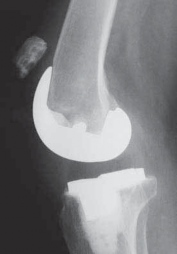

DEFINITION The knee classically has been divided into three compartments. Unicondylar knee arthroplasty (UKA)…